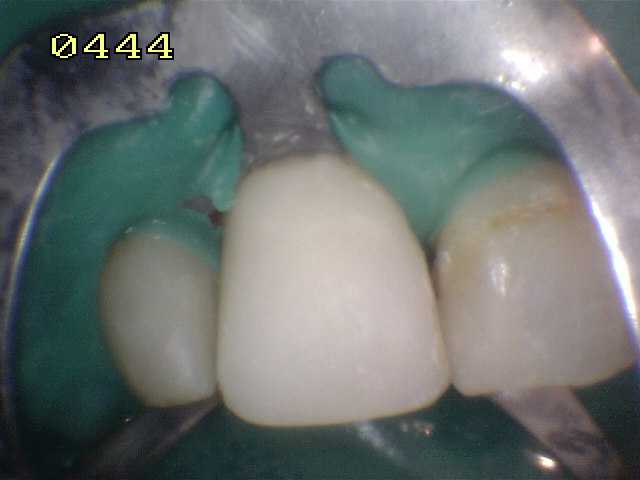

Conformación de la

corona con tiras de celuloide y pulido con discos de papael

y fresas multifilos |

Pulido con pasta

Dentbrill y brochita |